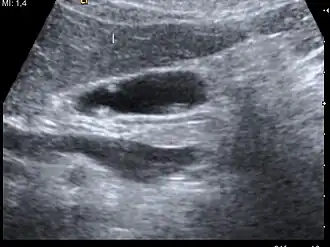

Diagnosis is typically by ultrasound or CT imaging.

Ultrasound image of gallbladder polyps measuring 3–7 mm. -